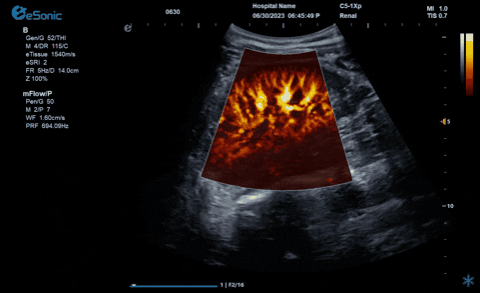

析“微”查异,识“微”见远

百乐博平台医疗的eHertz系列彩色多谱超声诊断系统凭借强大的RawVision?原数精准平台和SDBeam?软波声束合成技术推出专属的mFlow ?超微血流显像技术,该项技术可专用于极低速血流成像。彩色多普勒血流(CDFI)检查时,通常会将滤波器的频率设置为大约50hz,并随时调整标尺和增益,以便在背景噪声发生前显示小血管......